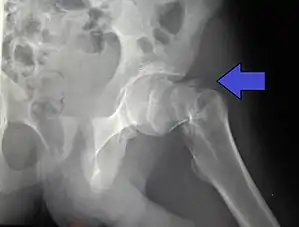

| Other names: Proximal femur fracture[1] | |

| Intertrochanteric hip fracture in a 17-year-old male | |

X-rays of the affected hip usually make the diagnosis obvious; AP (anteroposterior) and lateral views should be obtained.